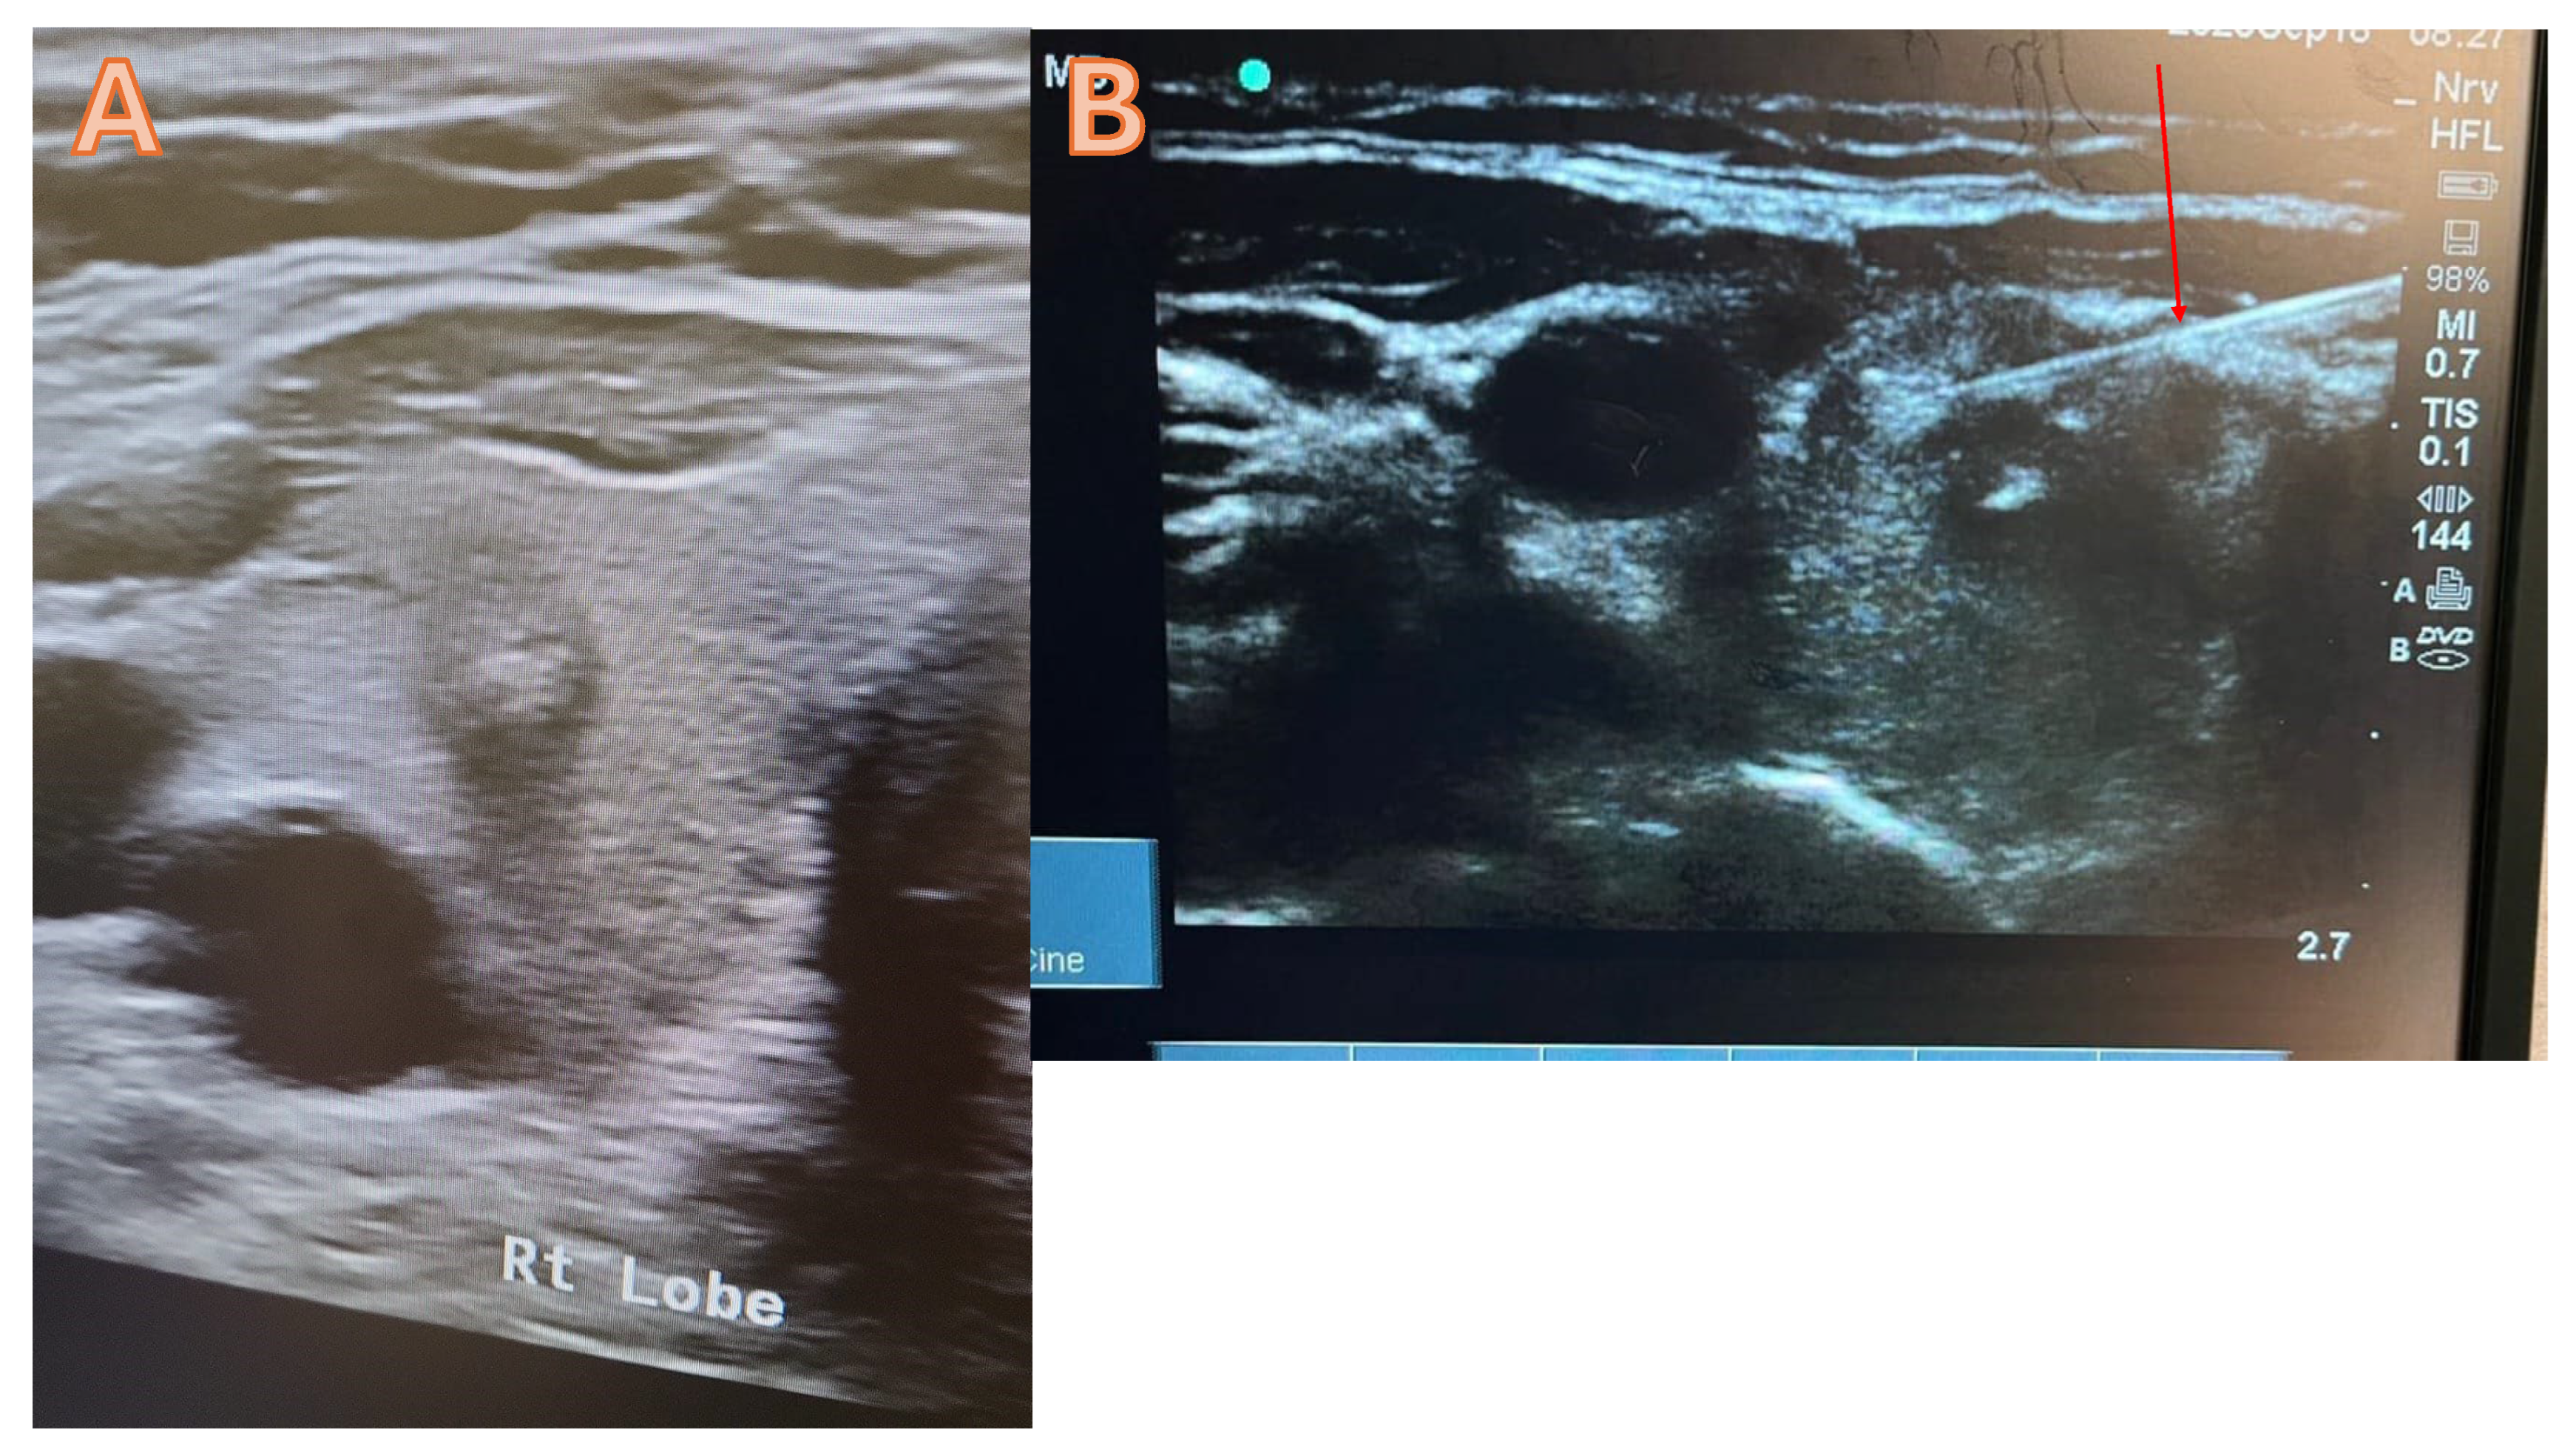

Typically, the thyroid FNAC is carried out under local anaesthesia in an outpatient setting with ultrasound guidance. In order to complete the procedure, fasting is not required. A thorough explanation of the procedure will be given to the patient by using pictures and video, and then a consent form will be obtained. Starting the procedure with the use of high-resolution ultrasound to determine the dominant nodule that requires FNAC (figure 1 a). After cleaning and sterilising the area, administer 1 mL of lidocaine (2%) to the intended site. The next step involves the trans-isthmic insertion of a 21G needle into the thyroid nodules under ultrasound guidance, requiring multiple passes to ensure proper material delivery (figure 1B). Next, withdraw the needle and equally distribute the aspirate among the slides. Before the slides have dried, immerse them in a 95% alcohol container for 30 minutes to guarantee sufficient fixation. Afterwards, the pathology lab will get the slides and proceed with their analysis. At the injection site, a plaster and an Eis pack will be applied. The patient will be monitored for thirty minutes before being discharged.

Figure 1. A high-resolution ultrasound suggests a potentially malignant tumour in the right lobe of the thyroid, categorised as Tirad 4. B= FNAC trans isthmic, the red arrow denotes the accurate placement of the needle into the nodule.